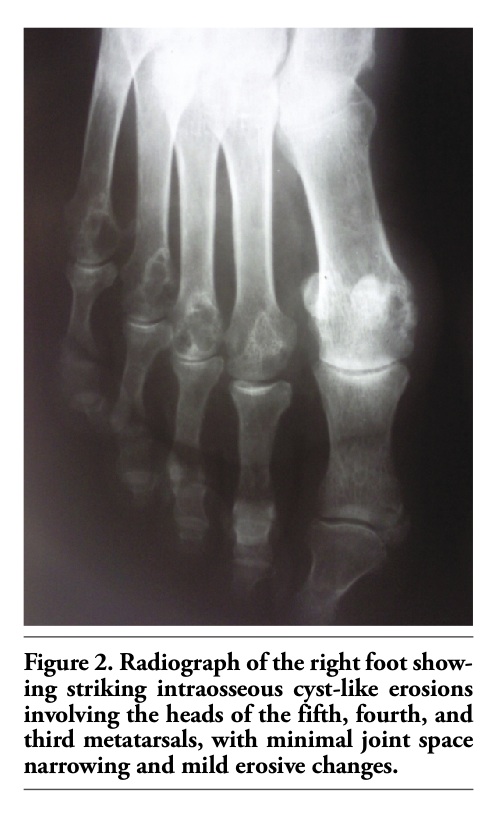

Laboratory tests showed the following results: ESR, 49 mm/h; white blood cell count, 9500/mm3; hemoglobin, 12.4 g/dL; SGOT, 31 IU/L; SGPT, 30 IU/L. Renal function was normal. Immunological tests were positive for RF. Radiology of the hands revealed subchondral geodes of the head of the third and fifth metacarpals with juxta-articular erosions and joint space narrowing in the second and third MCP joints bilaterally. No demineralization was observed. Radiographs of the feet showed intraosseous cyst-like erosions involving the head of the fifth, fourth, and third metatarsals bilaterally with minimal joint space narrowing and mild erosive changes (Figure 2). Radiology of the elbows was normal. Chest radiographic findings were normal.

Figure 2. Radiograph of the right foot showing striking intraosseous cyst-like erosions involving the heads of the fifth, fourth, and third metatarsals, with minimal joint space narrowing and mild erosive changes.